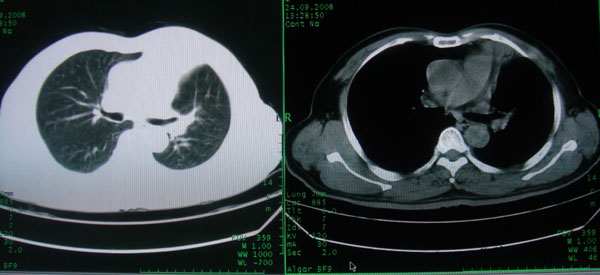

患者男性58岁因二周前起咳嗽,今天胸片示左上肺占位性病变行ct检查,无发热,无咯血痰.

左上肺感染性病变,结核伴空洞形成可能,左上肺膨胀不全

左肺上叶病灶,实变但见含气支气管、空洞但未见壁内结节及积液;

考虑:①感染性病变(包括特殊感染型肺tb)

②肿瘤性病变(考虑患者年龄比较大的关系/所以不排除)

初学者。。。左肺空洞性病变,并可见阻塞性肺不张改变,鉴于患者为老年男性,且临床症状仅有咳嗽,全身中毒症状不明显,所以我首先考虑为左肺癌性空洞并左侧肺门淋巴结转移伴左肺阻塞性肺不张。结核性空洞放于第二位考虑,可以进行相关实验室检查。希望能有病理结果,谢谢!!!!!

左肺上叶实变影,内见支气管充气征及空洞影,病人年龄较大,无发热及结核中毒症状,心影左移,未见纵隔淋巴结肿大;不知实验室检查结果如何?有否嗜酸细胞增多,有没有进行治疗?就目前资料首先考虑1.感染性病变,2.慢性嗜酸性肺炎?可结合实验室检查并短期治疗复查,肺癌不能排除。